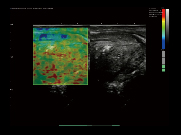

前列腺,弹性成像